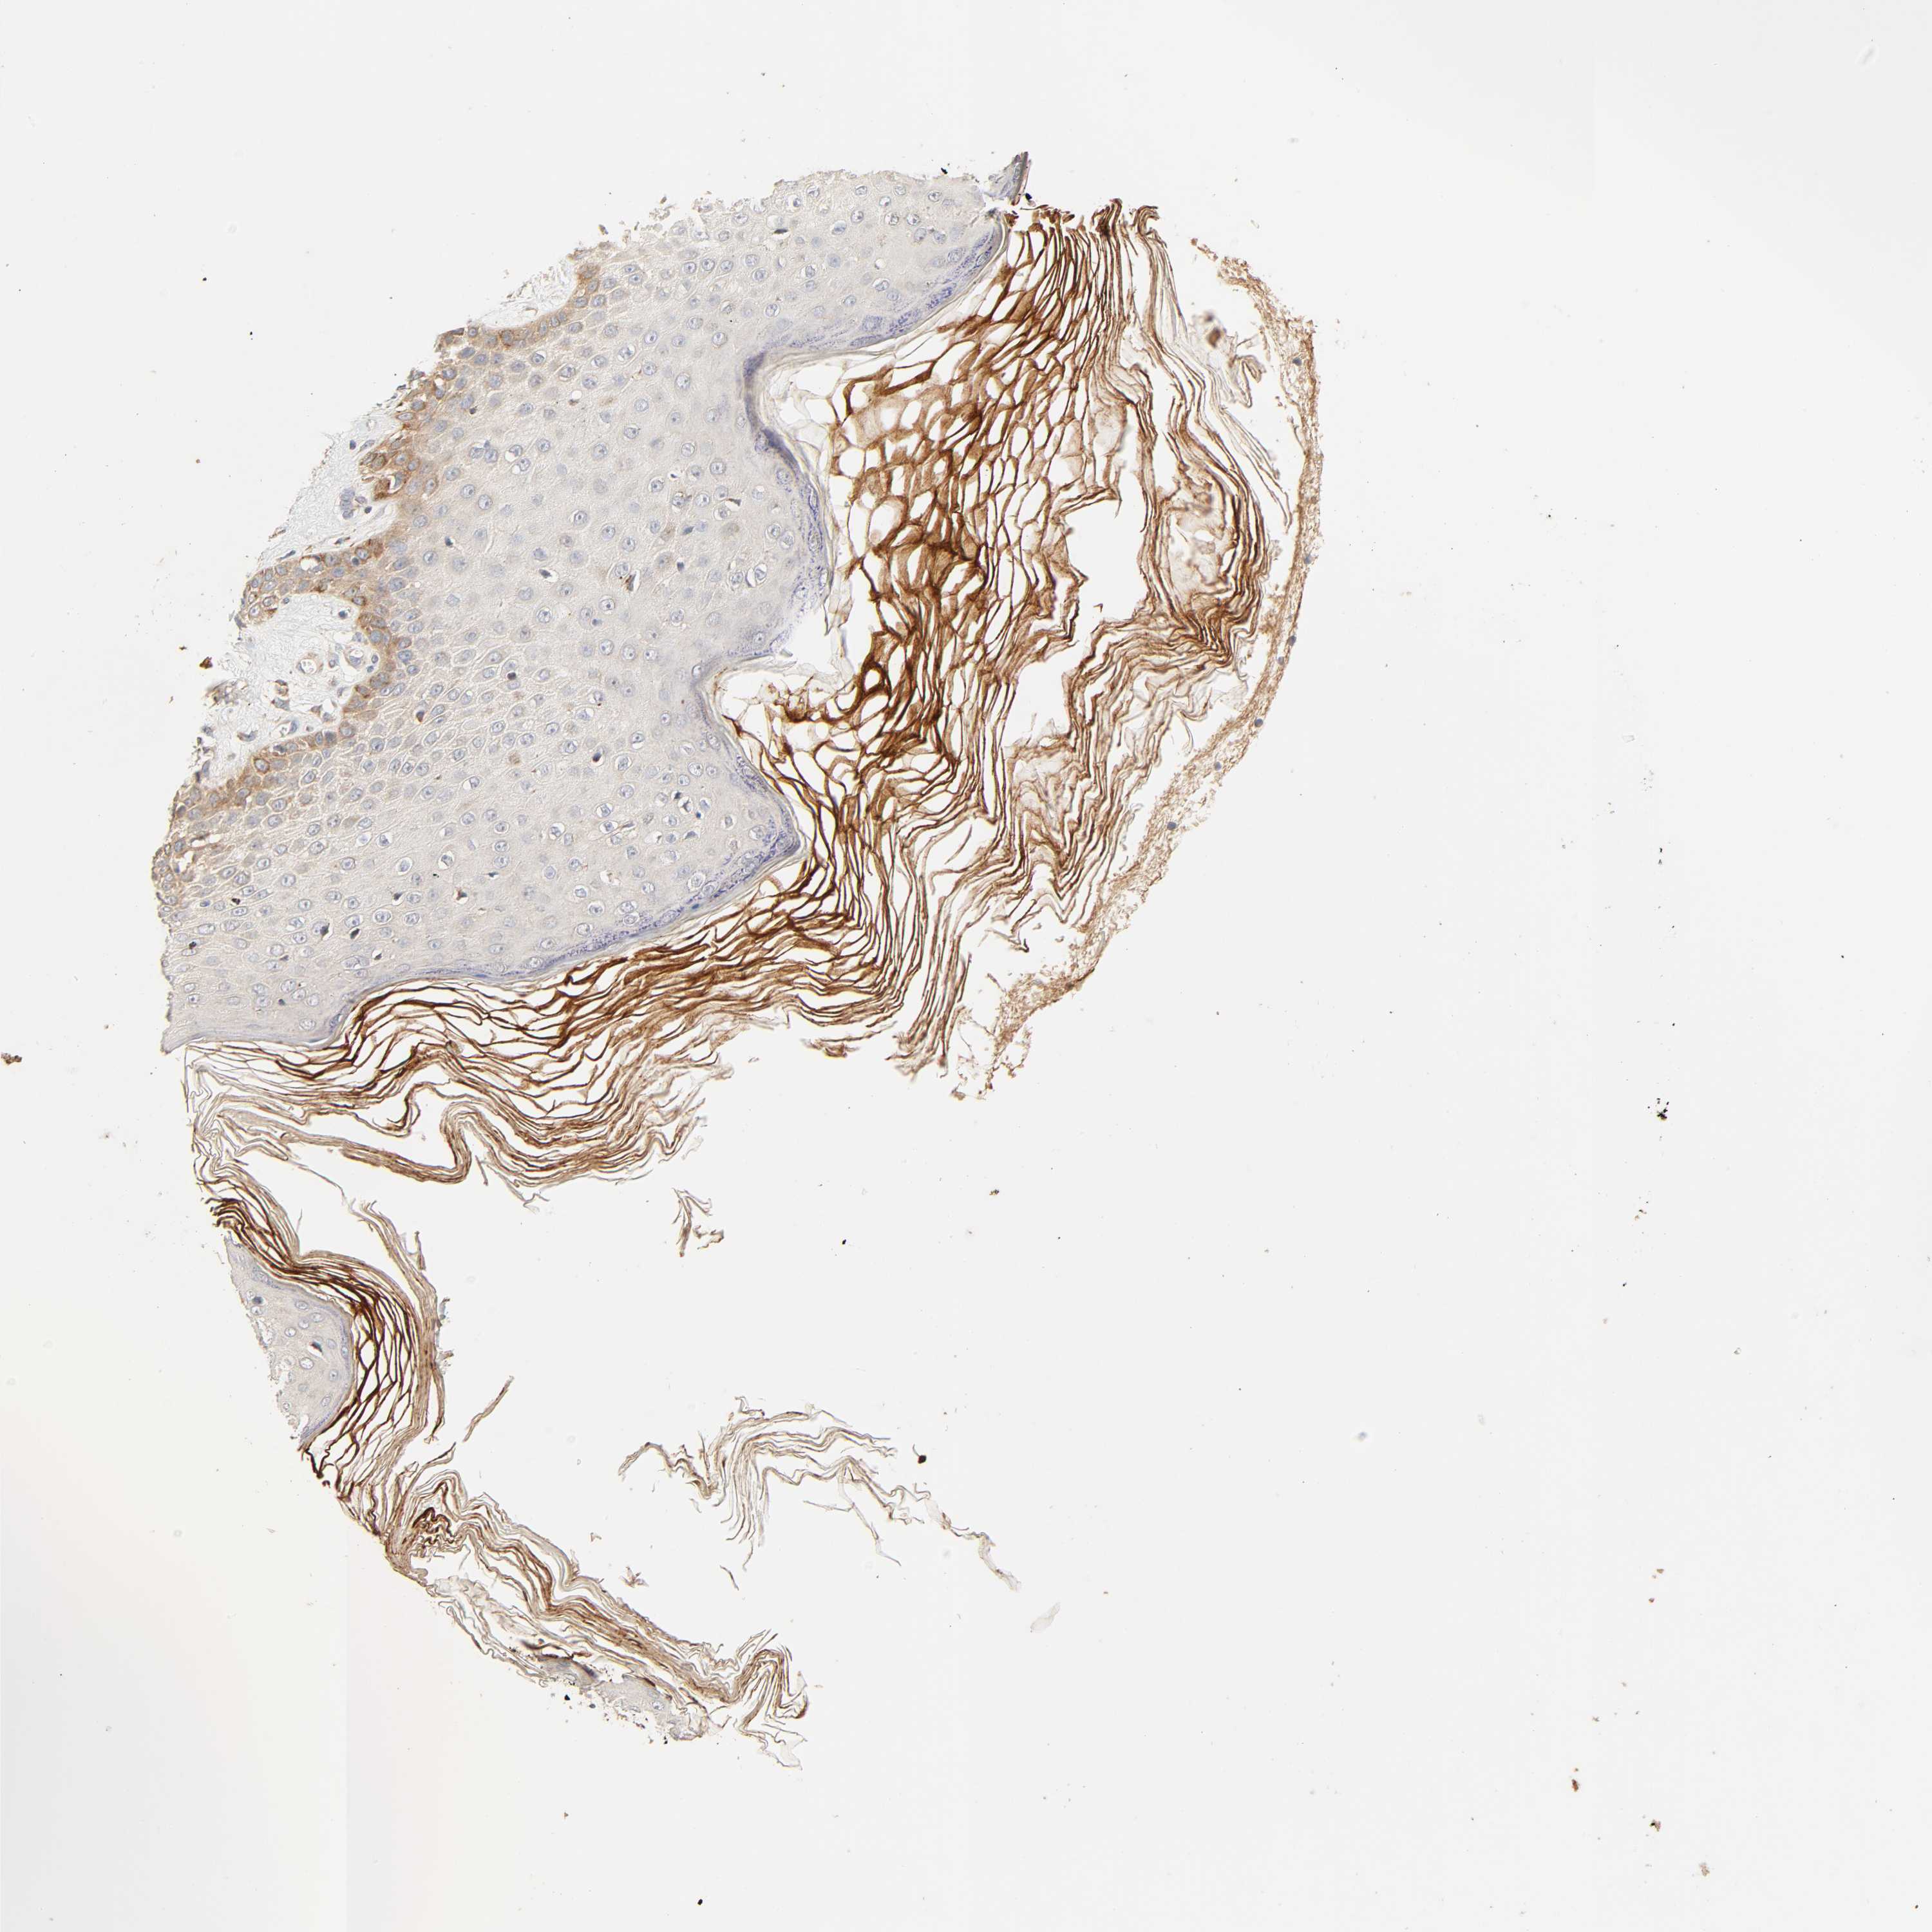

Basal cell and squamous cell cancer

SKIN CANCER - Protein expressioni

A mouse-over function shows sample information and annotation data. Click on an image to view it in a full screen mode. Samples can be filtered based on level of antibody staining by selecting one or several of the following categories: high, medium, low and not detected. The assay and annotation is described here.

Each image is clickable and will lead to virtual microscopy that enables deeper exploration of all samples and also displays staining intensity scores, fraction scores and subcellular localization as well as patient and tissue information for each sample.

Antibody HPA030262

Antibody HPA047825

Antibody CAB005184

Basal cell carcinoma

Squamous cell carcinoma, NOS

Squamous cell carcinoma, metastatic, NOS